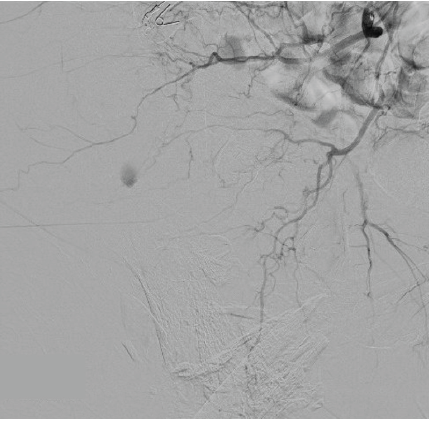

The patient had active extravasation from the SGA on CT scan. Interventional radiology (IR) was contacted, and emergent embolization was planned (Fig. 6).

Figure 6: Anterograde hip angiogram via fluoroscopy depicting superior gluteal artery extravasation before emergent embolization.

The patient was taken to the IR suite and the arterial branch supplying the area of extravasation was embolized with Gelfoam to cessation. The right common iliac artery, internal iliac artery, posterior division, and seven additional high-order vessels including the superior gluteal artery region were embolized. Hemostasis was confirmed under fluoroscopy.